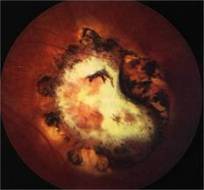

Toxoplasmosis is a disease provoked by the obligate intracellular protozoan Toxoplasma gondii. It is found in a variety of mammal and bird hosts. The most common intermediate host is the cat. It is one of the most frequent causes of retinochoroiditis in humans, with more than 60 percent of the United States population and up to 75 percent of the world's general population possessing some seropositive findings Etiology

Ophthalmic Features

Treatment